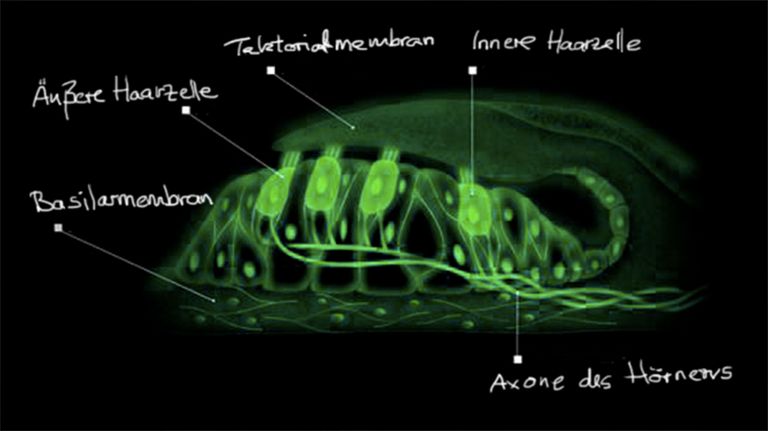

- Wahrnehmen

- Hören

Vom Wackeln zur wunderbaren Vielfalt der Klänge

Es ist ein langer Weg von rein mechanischen Schwingungen zur Welt der Klänge und Töné.

27.07.2012